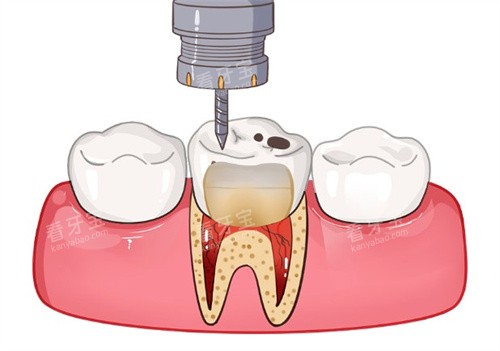

项目名称参考价格(元)说明简单充填(树脂)120 - 280浅龋、中龋复杂充填300 - 600深龋、需垫底根管治疗(前牙)500 - 9001-2个根管根管治疗(后牙)800 - 15003-4个根管显微根管治疗1500 - 3000疑难病例